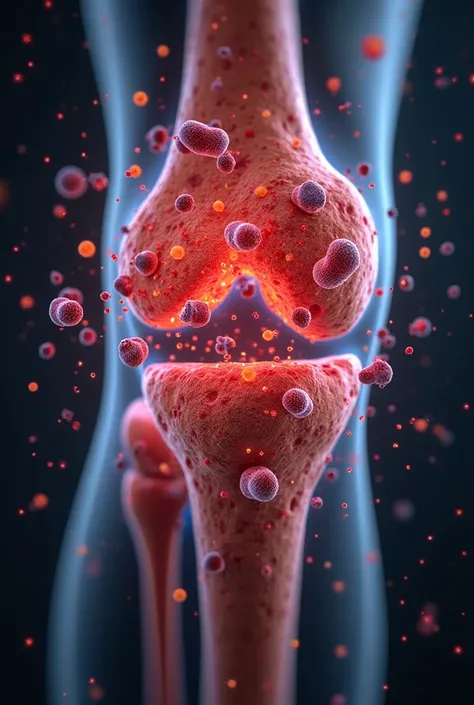

Create a realistic image depicting muscle pain in the leg. Show a person in a na

Create a realistic image depicting muscle pain in the leg. Show a person in a natural posture, with one hand placed on the area where you feel muscle pain. The area of pain should be highlighted with a reddish hue to indicate discomfort.. The person's expression should reflect mild distress or discomfort.. The image must have realistic skin textures and lighting., and the background should be neutral to focus attention on the person and the highlighted area of pain

Create a realistic image depicting muscle pain in the leg

Show a person in a natural posture

with one hand placed on the area where you feel muscle pain

The area of pain should be highlighted with a reddish hue to indicate discomfort

s expression should reflect mild distress or discomfort

The image must have realistic skin textures and lighting

and the background should be neutral to focus attention on the person and the highlighted area of pain